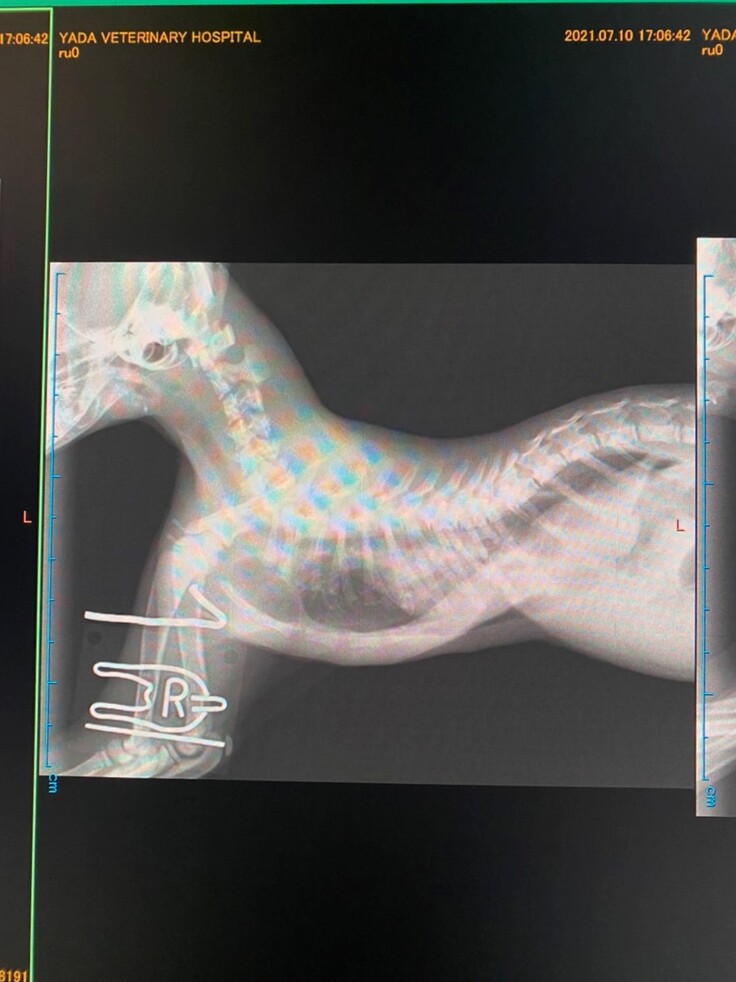

動物病院で検査のために撮られたレントゲン。

胸骨が大きく湾曲していることがわかります。

下が手術前、上が手術後のレントゲンです。

胸の骨がまっすぐになりました!